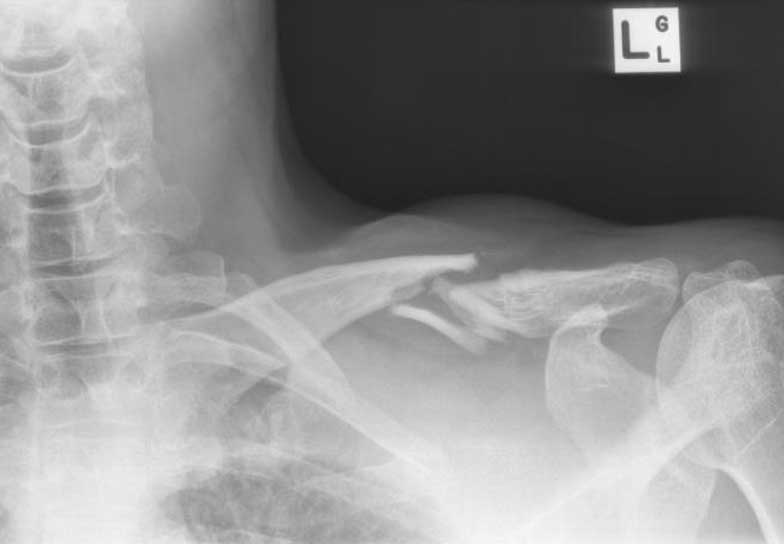

What do clavicle fractures look like on X-ray?

Below are examples of typical fractures that benefit from surgery.

Click an image to enlarge